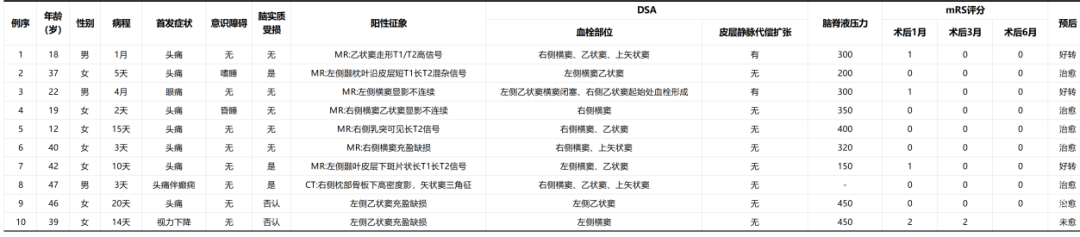

患者,女,28岁,以“突发头痛,伴恶心、呕吐间断发作7天”为主诉入院。患者家属代诉患者于7天前无明显诱因突然出现剧烈头痛,具体疼痛部位不详,患者自行在家艾灸后有缓解,3天后头痛再次发作,并伴呕吐,遂于我院急诊科行头颅CT扫描提示左侧额叶可疑小稍低密度,急诊血常规+有核红:血红蛋白81.00(g/L)↓,血小板计数541.00(10^9/L)↑,未行特殊治疗,返回家中,呕吐加重。次日再次因头痛来我院就诊,逐渐出现意识障碍,于急诊科行头部MRI提示:左侧丘脑、双侧半卵圆中心、双侧顶叶及右侧额叶深部白质区多发异常信号,考虑脑血管病-亚急性期脑梗死可能,脑炎待除外,完善腰穿脑脊液送检,脑脊液常规未见异常,于10月26日行MRV提示:直窦、左侧乙状窦、左侧横窦未显影,考虑静脉窦血栓,患者持续意识障碍,表现为呼之不应,查体不合作,遂请神经外科会诊,完善头颈部CTA提示:2023-10-27双侧丘脑、双侧半卵圆中心、双侧顶叶及脑干多发斑片状低密度影,考虑脑梗死可能性大。

患者入院急诊完善MRV提示:左侧横窦、乙状窦、直窦血流信号充盈缺损,考虑静脉窦血栓形成(图二)。

诊治经过

术后1周患者专科查体:神志清,对答切题,定位定向准确,双瞳等大、等圆,光反射灵敏,四肢肌力肌张力正常。术后脑脊液压力:150mmH₂O。

术后1月患者随访MRV:MRV可见右侧横窦、乙状窦可见血流信号,较前好转。

患者系28岁年轻女性,否认近期生产史,否认长期口服避孕药物史,入院后患者神经系统查体提示患者存在意识障碍,伴有肢体活动障碍。完善相关辅助检查后考虑患者颅内静脉窦非化脓性血栓形成。